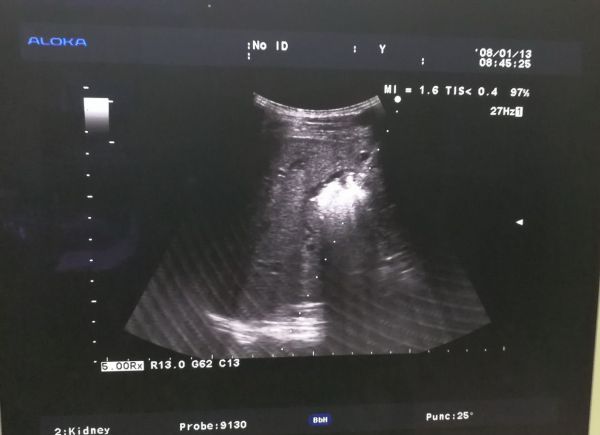

B型超声检查的范围很广,不同的检查部位,检查前的准备亦不相同。①腹部检查:包括肝、胆、胰、脾及腹腔等。一般应该空腹检查,因为进食后,胃及肠道产生气体,影响超声的穿透,空腹检查效果最好。②妇科检查:应该饮水憋尿,当膀胱充盈后,挤开肠管,让超声更好的穿透到盆腔,清晰的显示子宫及卵巢的正常与异常。③泌尿系检查:应该多饮水,当膀胱充盈后,内部的结石、肿瘤、息肉等,即能更好的显示。④体表肿物及病变:可以即时检查,一般无需特殊准备。⑤心脏及四肢血管检查,亦无需准备。